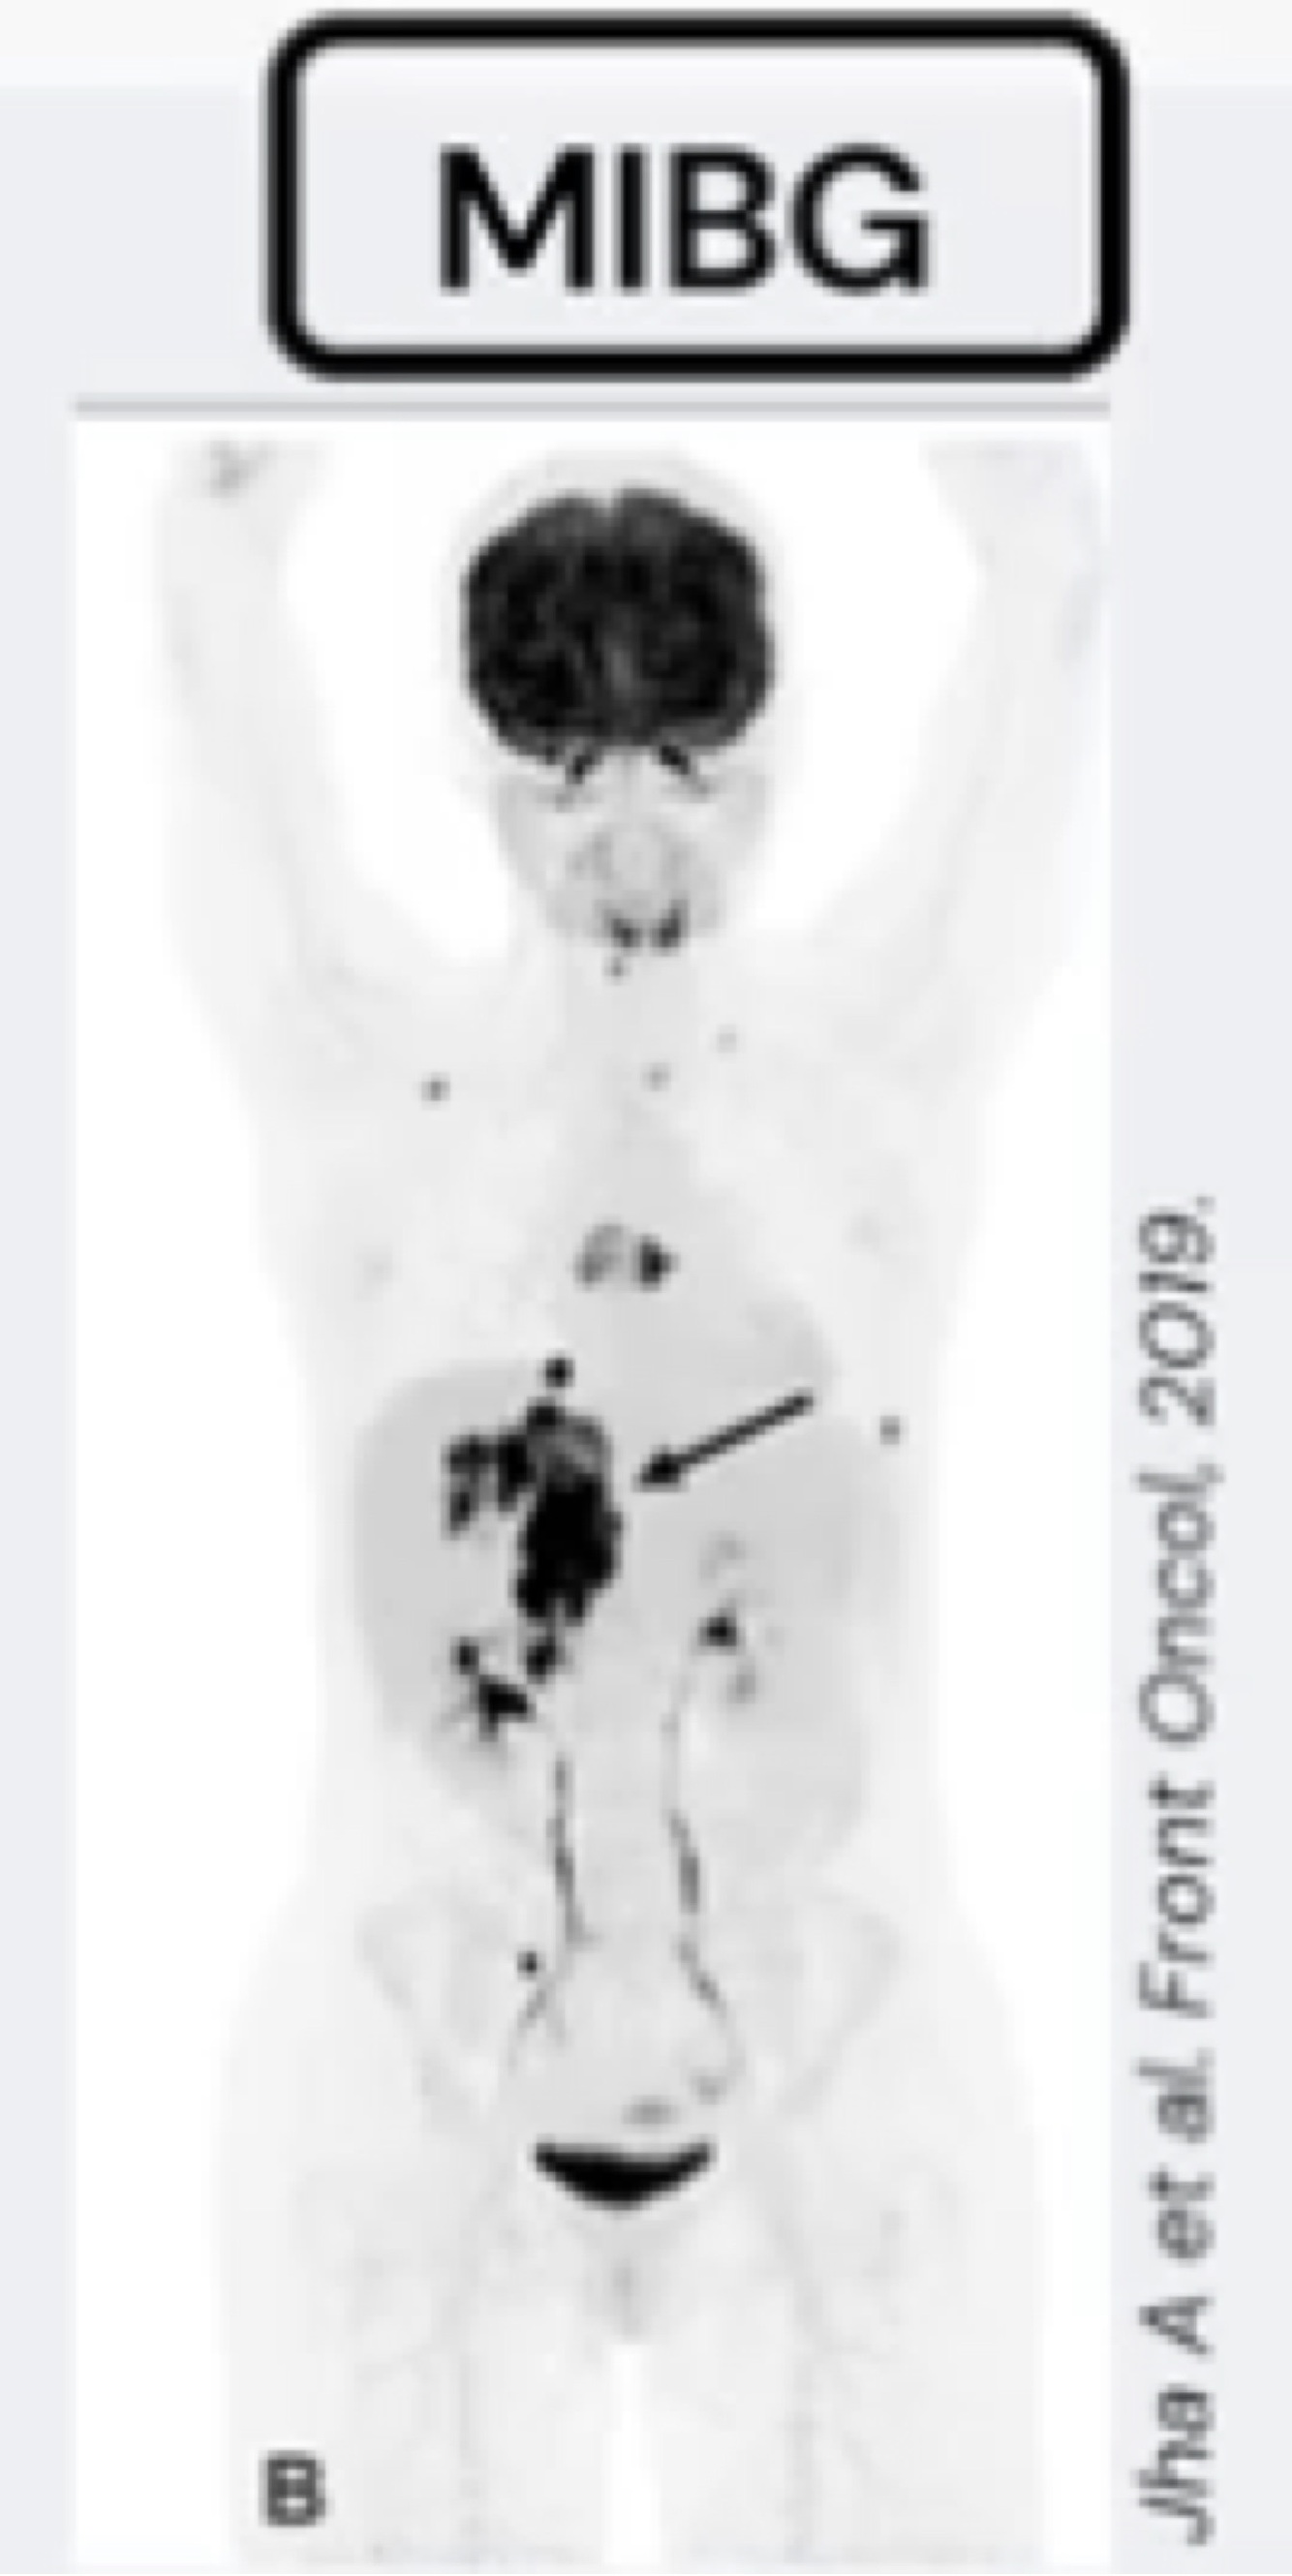

Q

Como investigar Feocromocitoma extra adrenais?

A

Cintilografia com MIBG.